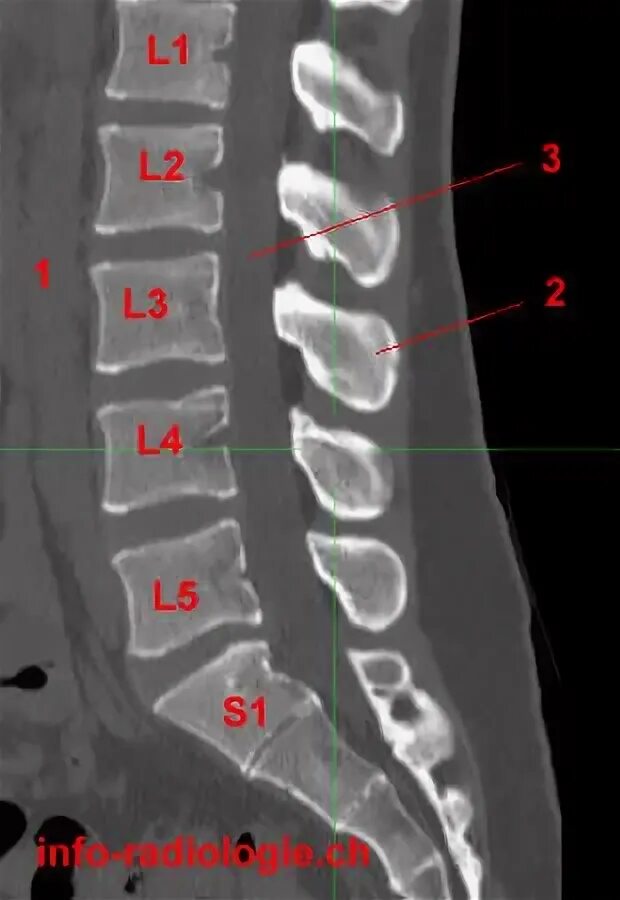

L 4 c 3